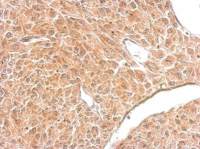

Immunohistochemical analysis of paraffin-embedded human gastric cancer, using RAB33B(GTX116390) antibody at 1:500 dilution.

Antigen Retrieval: Trilogy™ (EDTA based, pH 8.0) buffer, 15min